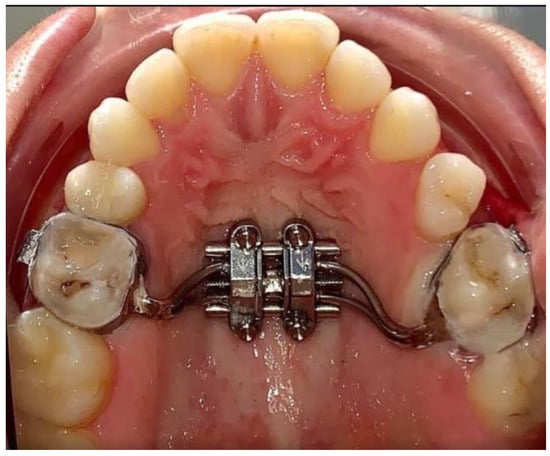

2. Material and Method

2.1. Outcome Measures

2.2. Clinical Outcomes